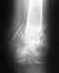

Подскажите наиболее эффективное лечение ложного сустава на месте соединения стержнем Кюнчера сломанной бедренной кости (верхняя треть). Есть ли альтернатива ЗАМЕНЕ стержня на пластину

(какие-нибудь дополнительные фиксаторы неподвижности обломков в добавок к уже установленному стержню)? Как долго стержень Кюнчера можно не удалять без вреда здоровью?Вероятны ли повреждения несросшихся фрагментов кости при вытаскивании стержня Кюнчера?Препятствует ли стержень Кюнчера удалению новообразований, мешающих срастанию? если мешает, возможно ли вместо полного извлечения - частичное с последующим обратным забиванием и соединением фрагментов кости?Желаю всем здоровья.